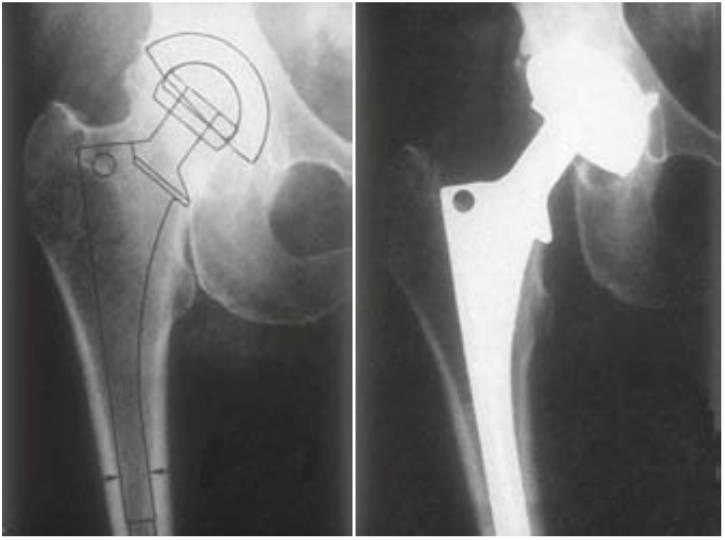

En el campo de la ortopedia, la sustitución de la articulación de la cadera presenta diferentes complicaciones, incluyendo la infección de la cicatriz, la fractura periprotésica, la luxación, el fracaso mecánico y la osteólisis. La osteólisis se refiere a la reabsorción ósea que se produce alrededor de los implantes ortopédicos cementados y no cementados (fig. 4-25).

La pérdida aséptica de la interfase hueso-implante a causa de la osteólisis es la causa más importante del fracaso tardío de la sustitución de la articulación (10% durante los 10 primeros años). A esta condición están asociados primariamente factores mecánicos de carga. Los factores del paciente que aumentan el fracaso de la carga incluyen el peso corporal y el nivel de actividad. Un modelo animal y un informe humano han relacionado la reabsorción del hueso en la interfase con la sobrecarga mecánica. El tratamiento del desorden, si el paciente está asintomático con una amplia afectación osteolítica pero sin movilidad del implante, incluye un curetaje de la membrana osteolítica y un injerto óseo. Estos informes ortopédicos aceptan que la sobrecarga mecánica puede ser la causa de la reabsorción ósea en la interfase hueso-implante. El metal más frecuentemente empleado en estas terapias de sustitución de la cadera es la aleación de titanio, y la interfase hueso-implante es muy similar al de un implante dental. Adicionalmente, elementos potencialmente causantes encontrados intraoralmente, como la contaminación oral bacteriana, la posición del microgap, y la pérdida ósea relacionada con microbios, son eliminadas en este entorno aséptico. Es lógico asumir que estos estudios soportan una posterior relación entre la pérdida ósea marginal alrededor de los implantes y el estrés biomecánico.